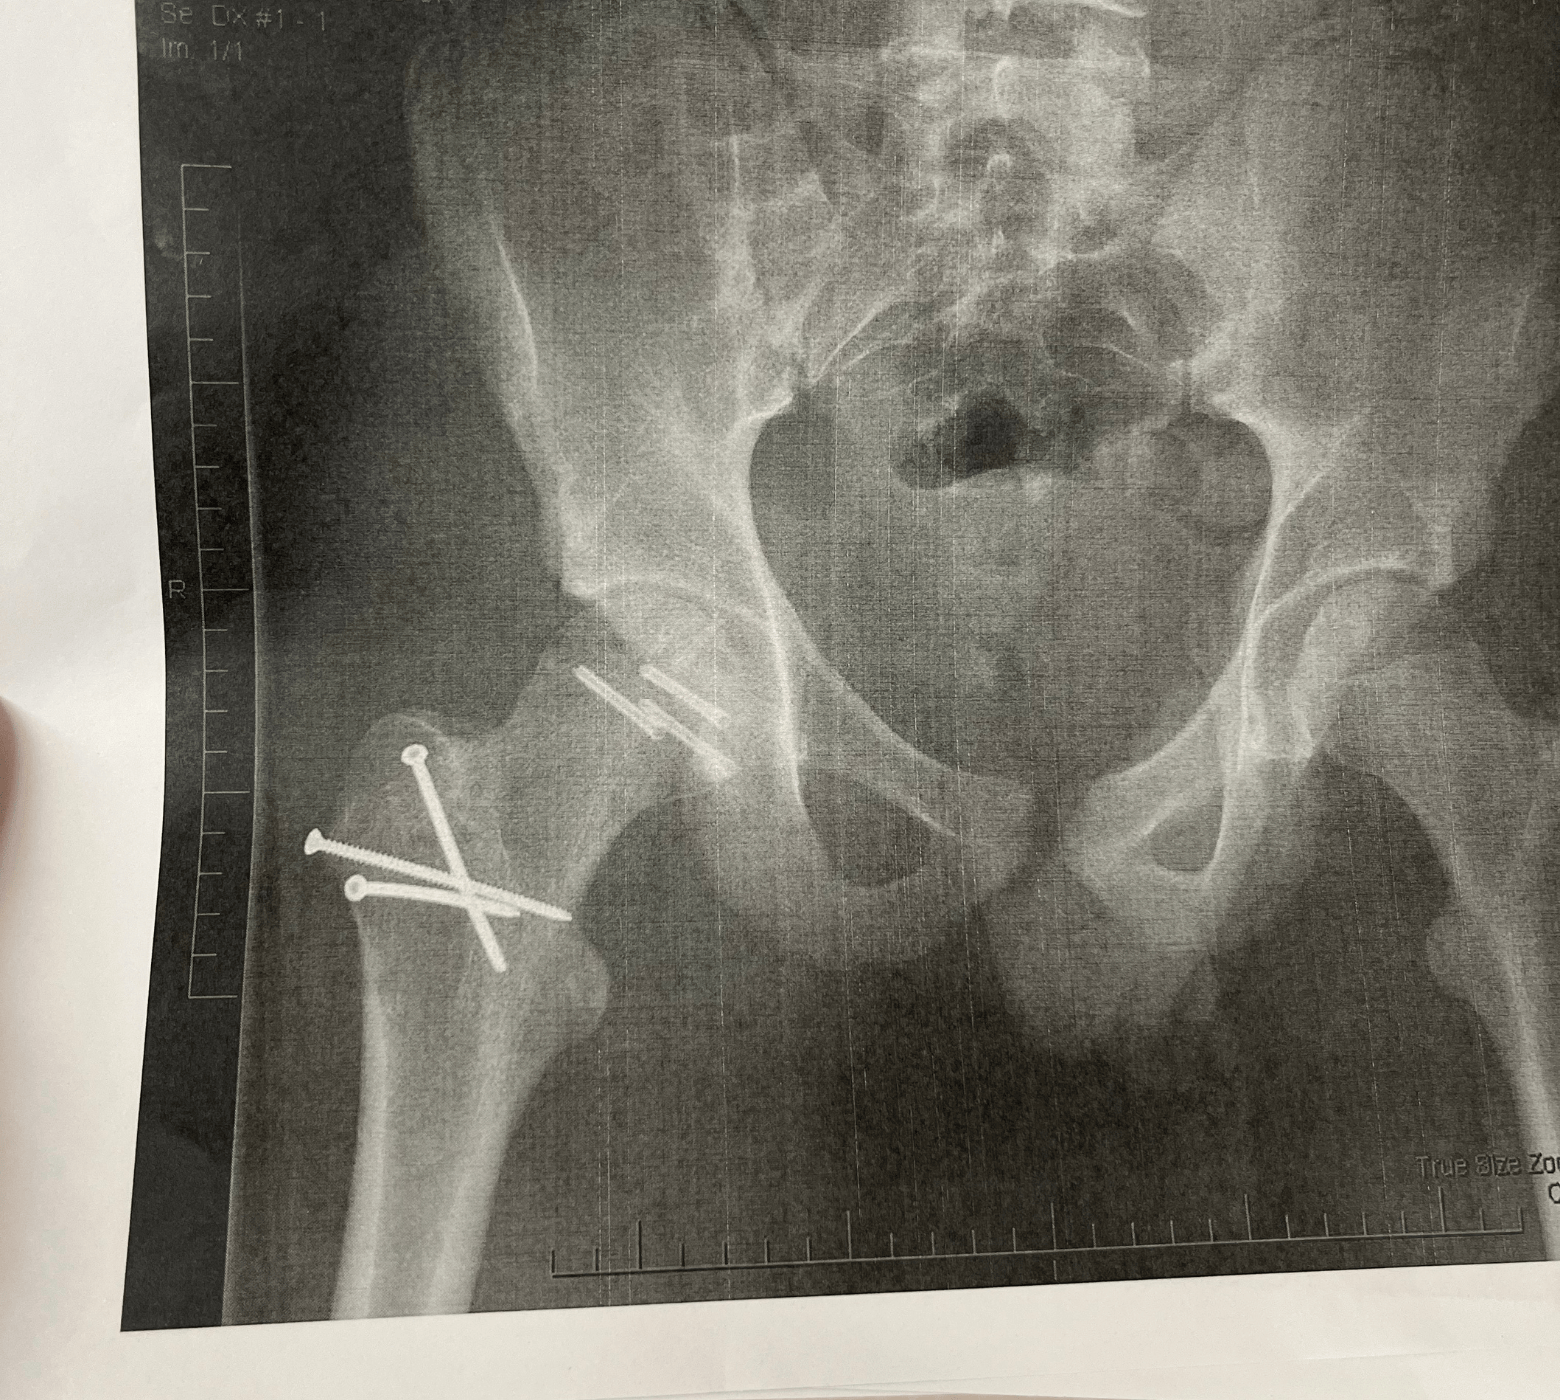

Riley had suffered a devastating injury. His hip was dislocated, and the top of his femur shattered. Surgeons worked to piece him back together, inserting eight metal pins to stabilise his leg. He spent three weeks in hospital and three long, difficult months unable to weight bear, slowly rebuilding his strength.

At a routine check-up a year later, the family heard more difficult news. X-rays showed that Riley’s hip wasn’t healing the way they had hoped. The bone was deteriorating. Arthritis had already set in, and the damage was severe, bone on bone.

Riley now faces the reality of needing a full hip replacement at just 17 years old. But he is determined to keep going, monitoring the pain, and pushing the operation out for as long as possible.

5 pins now hold the joint together

Riley's hip xray